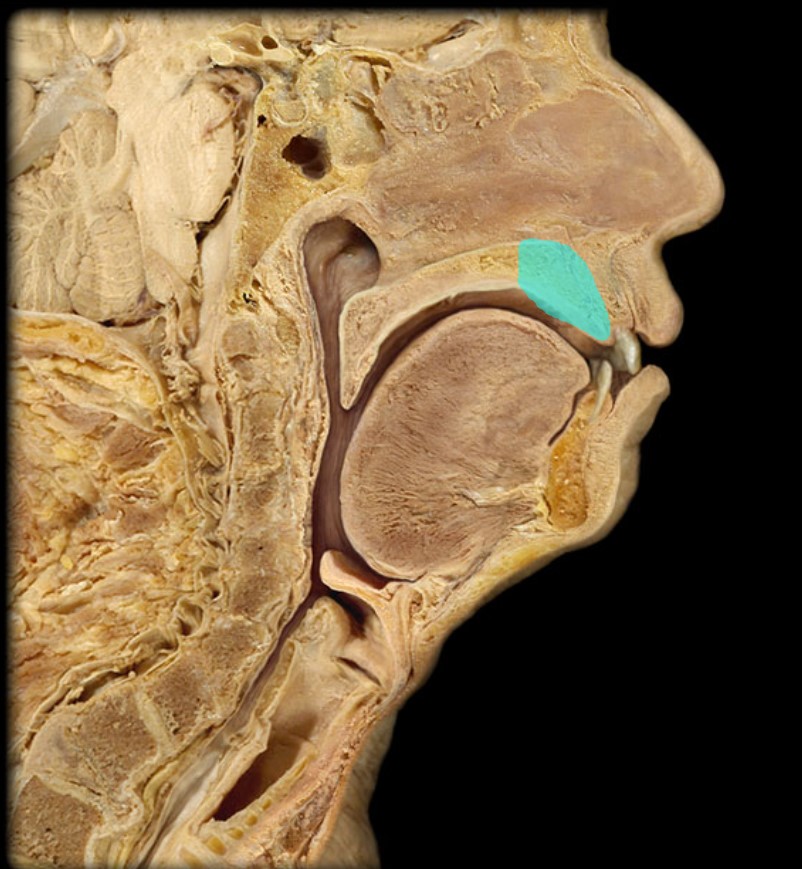

Palatine Tonsil

16

New cards

Uvula

17

New cards

Soft Palate

18